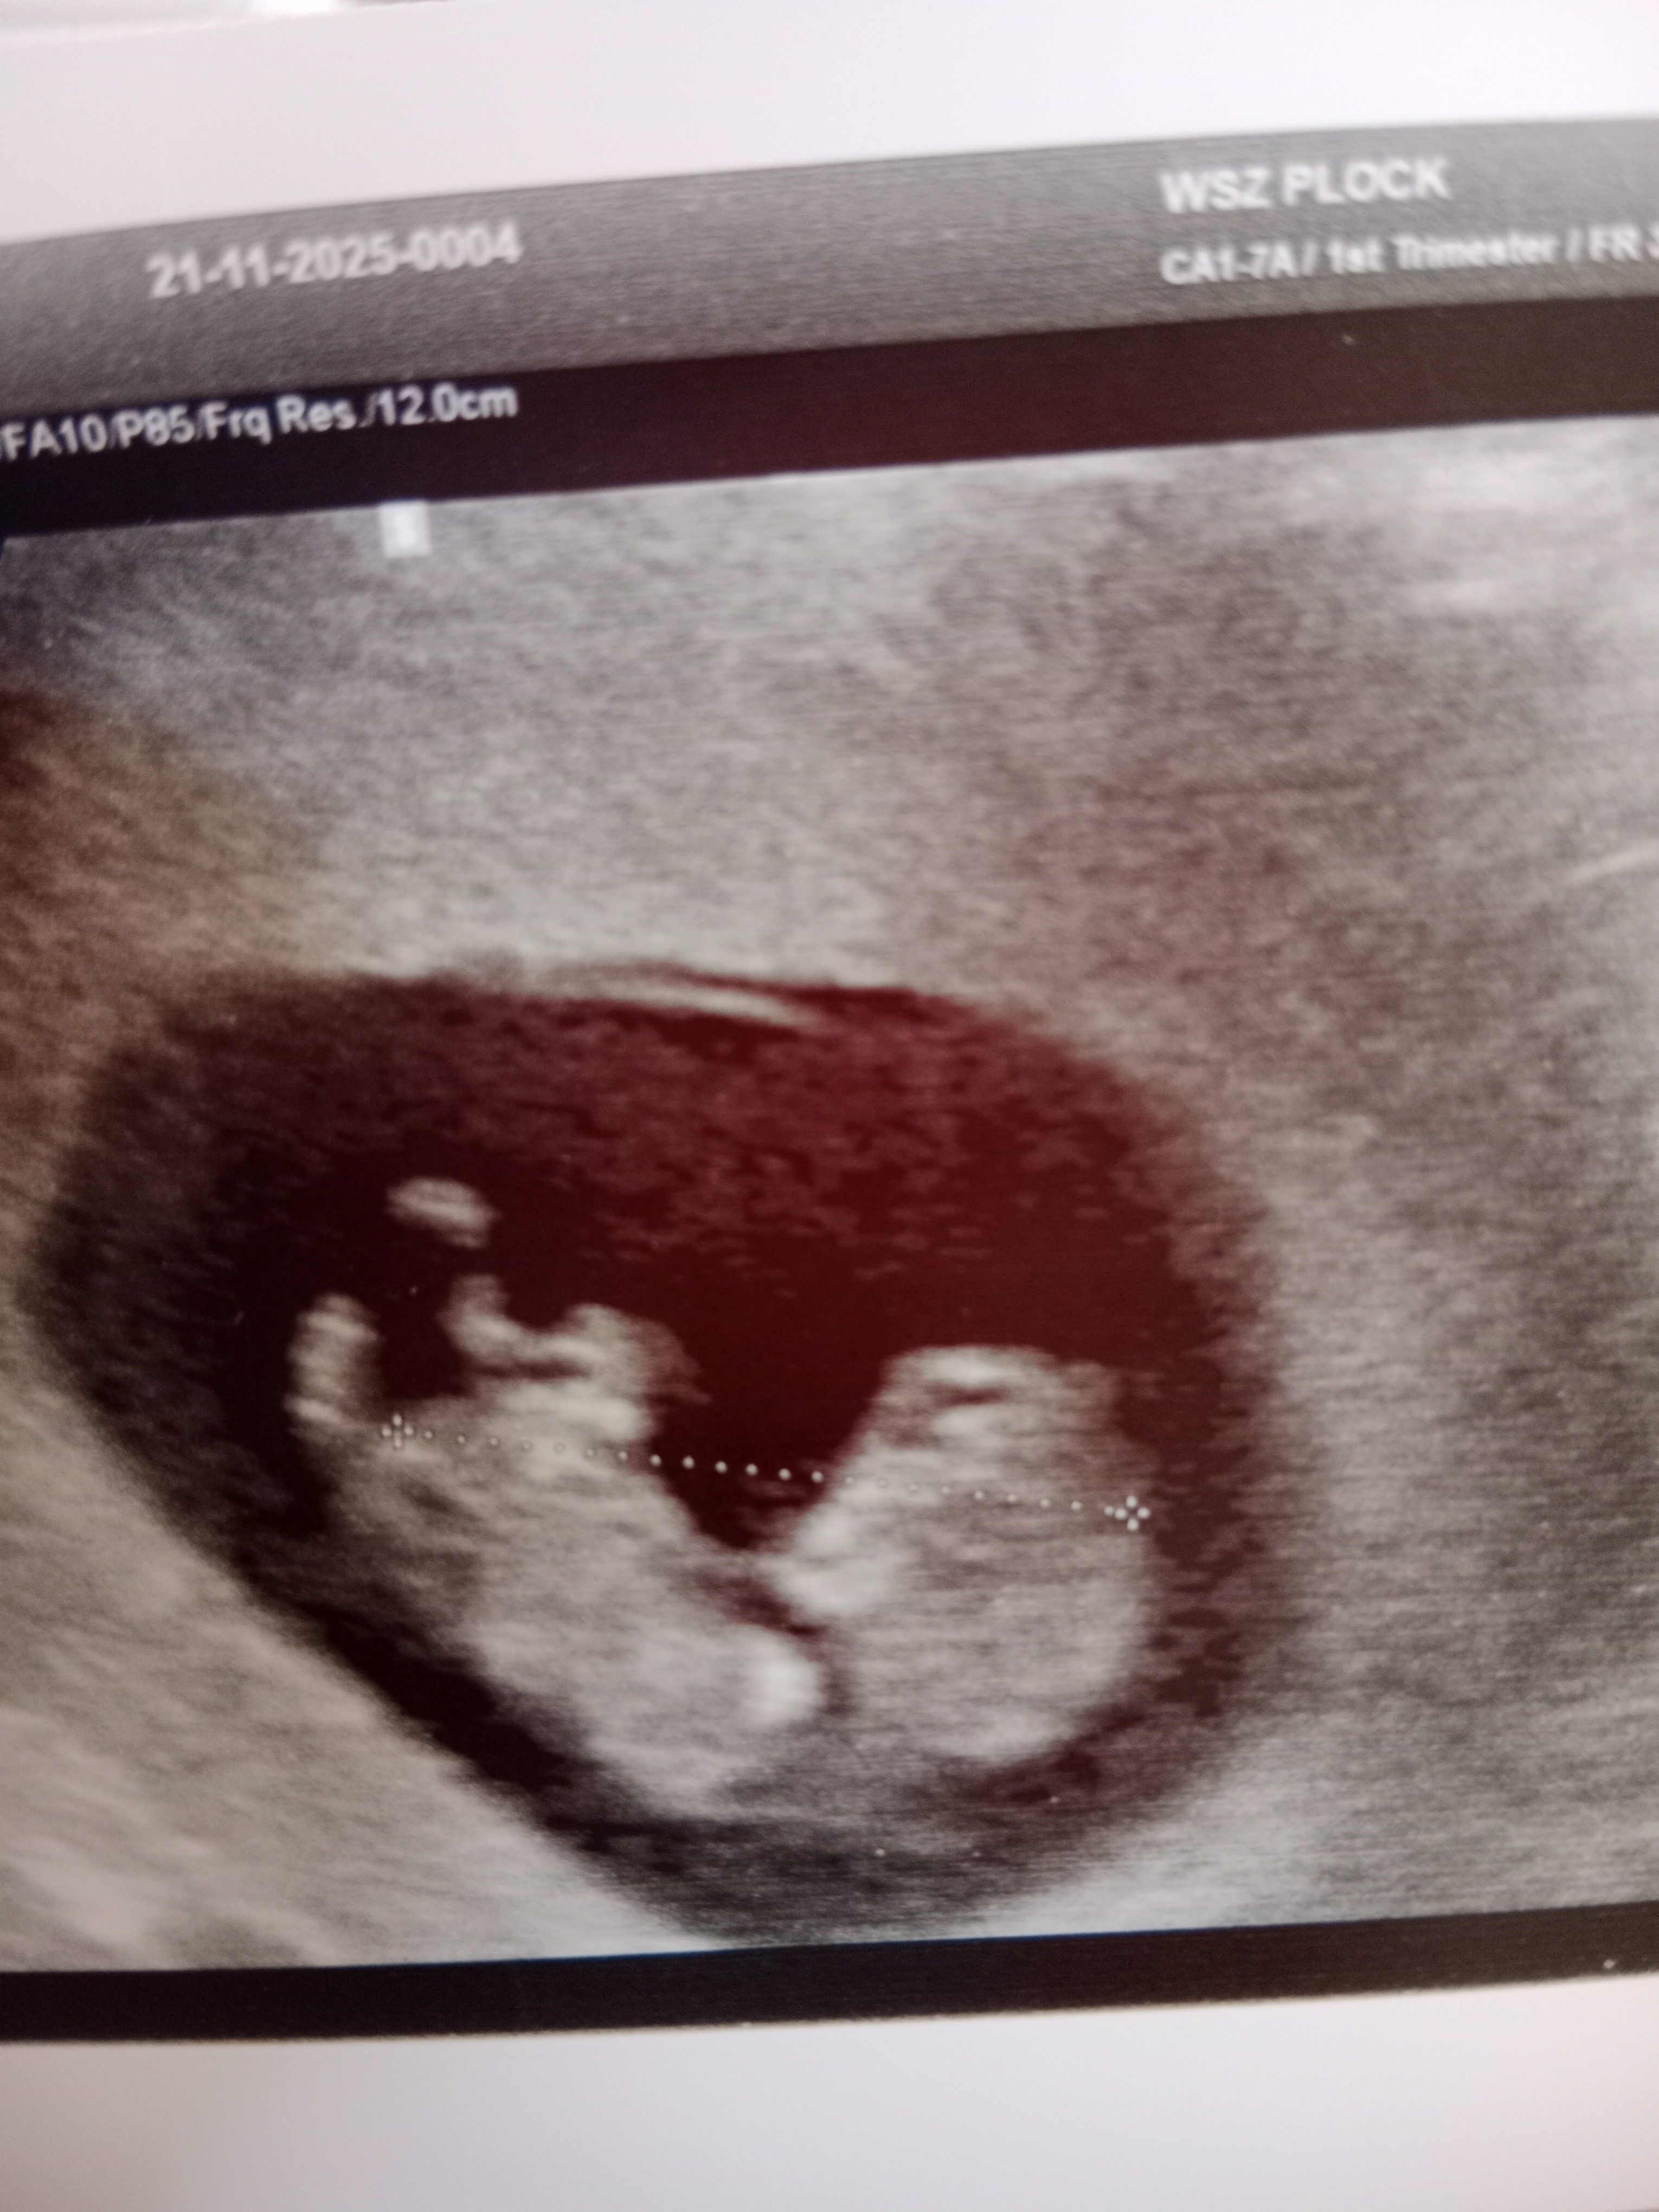

Hej :) wyszłam dzis że szpitala, zwiększyli mi po prostu dawkę dopegytu i mam się oszczędzać. Nie dostałam wypisu więc nie wiem jak wyniki wszystkich badań ale na pewno powiedział że ponoć jestem po cytomegalii ale wszystko było na szybko załatwiane bo mieli dzisiaj kocioł. Miałam na odchodne USG przez brzuszek już i dostałam zdjęcia pamiątkowe :D dzidzia sobie majta rączkami i nóżkami. 6 grudnia mam USG genetyczne i pappa a 16 grudnia kolejna wizyta 🥹♥️

• IMG_20251121_122024.jpg

IMG_20251121_122024.jpg

1,6 MB · Wyświetleń: 44